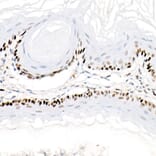

Immunohistochemistry analysis of paraffin-embedded human esophagus using Anti-PCNA Antibody [ARC51324] (A305487) at a dilution of 1:8,000 (40x lens). Perform high pressure antigen retrieval with 10 mM citrate buffer pH 6.0 before commencing with IHC staining protocol.